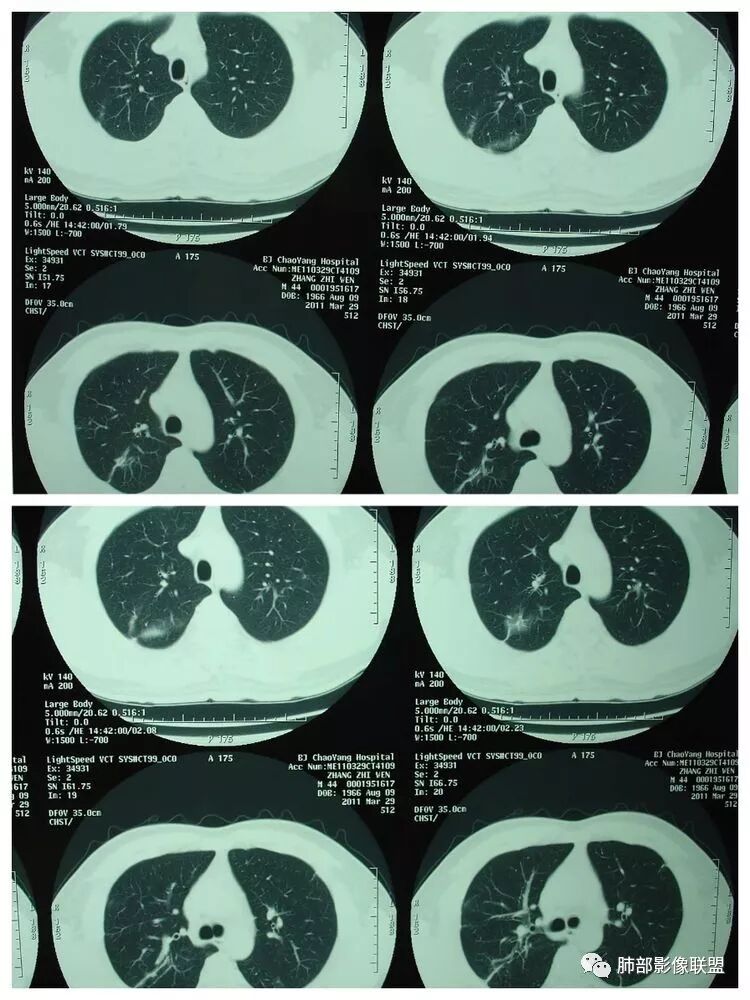

胸 CT

南边:胸膜下,类圆形,边界清,内有坏死,典型的反晕征,支气管壁增厚不明显,支持血道来源脓毒栓子所致梗死、感染

血道来源没问题

左下叶大片类似病灶

南边:反晕征是毛霉菌的特点按理单从影像:毛霉菌更多符合因为细菌性的特点:液气平面,囊,这个没出现

肺克的影像表现(唐绍宏总结):分布:单侧上叶病变,以右肺上叶多见;患者长期卧床则双脚下肺后基底段分布(国外下肺多见,可能与平均寿命长,卧床及住托老机构多有关) ;如多叶段病变,则以肺上叶后段或下叶后基底段为最明显形态:气管壁增厚、磨玻璃、小叶实变、节段实变、大叶实变,坏死小空洞(直径小于2cm) ,少量胸腔积液50%、脓胸20%特点:早期气管壁增厚较明显、广泛,越靠近病灶越明显,越靠近肺门越明显,见于实变病灶外,偶尔见于磨玻璃影内(支气管通气征) ;未经抗生素治疗,实变病灶内无支气管通气征;早期即可出现坏死,无论坏死还是空洞,绝大多数直径小于2cm (可能与此菌有厚夹膜有关,参考隐球菌)